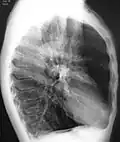

A chest X-ray is not useful to establish a diagnosis of COPD, but it is of use in either excluding other conditions or including comorbidities such as pulmonary fibrosis and bronchiectasis. Characteristic signs of COPD on X-ray include hyperinflation (shown by a flattened diaphragm and an increased retrosternal air space) and lung hyperlucency.[5] A saber-sheath trachea may also be shown that is indicative of COPD.[111]

Lung bulla as seen on chest X-ray in a person with severe COPD